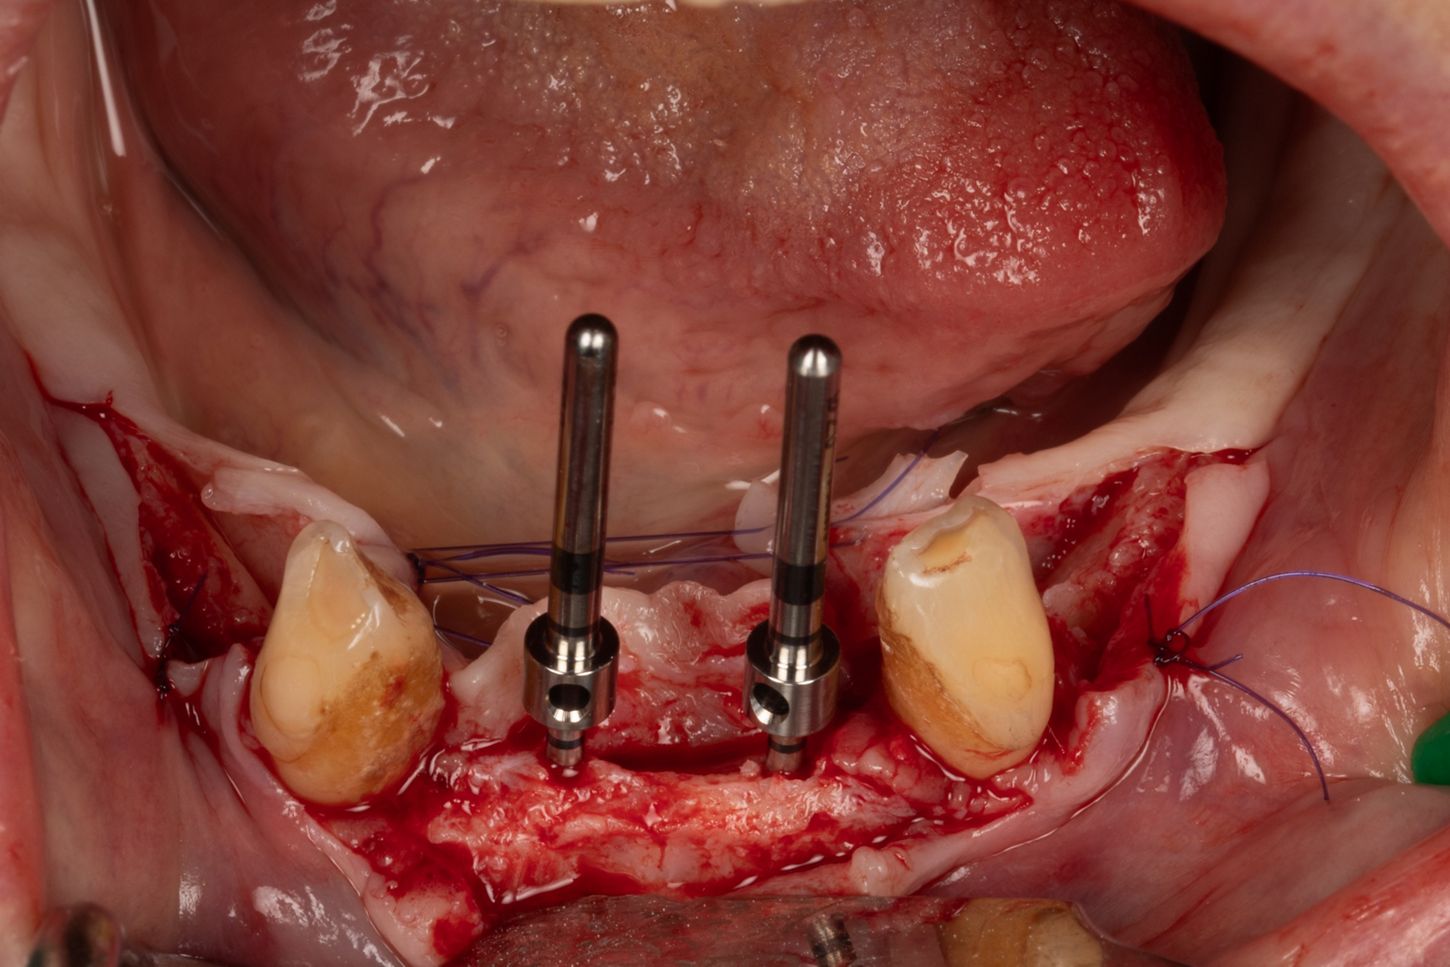

3d. Two mini-implants with a diameter of 2.6 mm and a length of 12 mm were placed in positions 34 and 44 using the same protocol as for the previous mini-implants. The torque obtained was 27 Ncm in 34 and 37 Ncm in 44.

3e. Canines 33 and 43 were extracted and the burial of the implants was then checked.

3e

3f. 5/0 absorbable sutures were placed around the mini implants, taking care to preserve as much keratinised tissue as possible around the Optiloc attachments.

3f